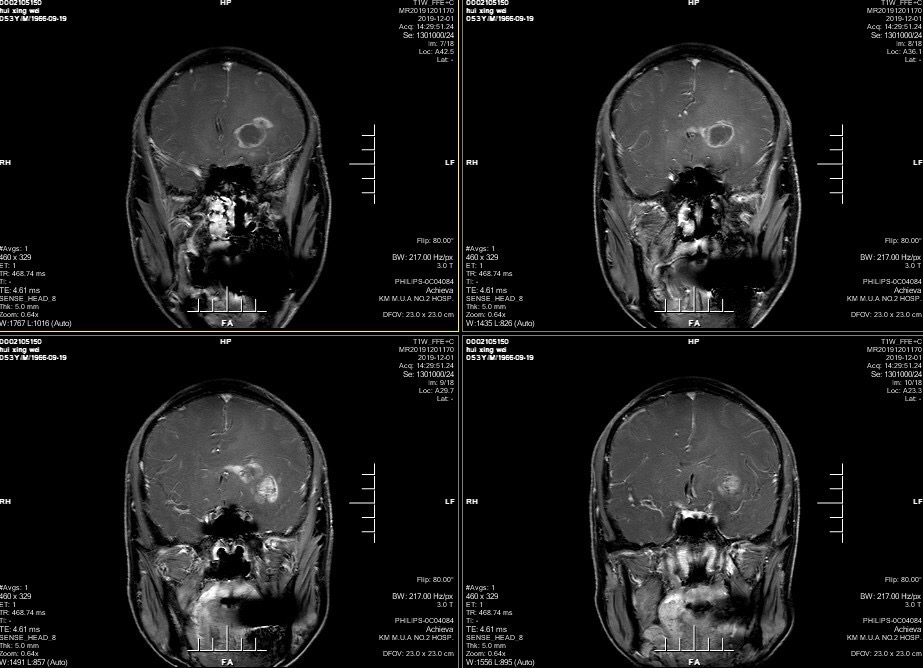

男性患者,53岁,主诉:反复头痛伴恶心一周,突发意识丧失一次。入院查体:神经体统无阳性体征。入院头颅MRI:左额叶胼胝体区囊实性占位,不均匀强化,考虑高级别胶质瘤;长程视频脑电监测提示左侧中央区、顶区、后颞区见中等量低-中-高波幅痫样放电。术前诊断:1.左额叶胼胝体区占位病变;2.继发性癫痫,入院给予降颅压及抗癫痫处理,积极完善术前准备后于2019年12月3日全麻下完成手术,术中行B超引导下切除肿瘤。术后患者无肢体功能及语言功能障碍,复查头颅核磁肿瘤全切,一周后出院开始放化疗治疗。

肿瘤为囊实性。

双侧大脑前动脉受肿瘤推挤。

增强后不均匀强化。